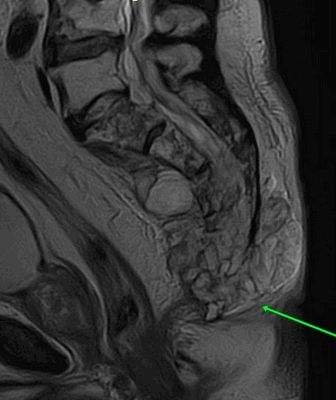

На рисунке - T2-Stir ВИ

Изменения выявляются в синовиальной (нижней и наружной) и в связочной (верхней и внутренней) частях сустава; в большей степени со стороны подвздошной кости.

На рисунке - отек структур полости суставов

На рисунке - отек капсулы суставов

На рисунке - отек ретроартикулярных связок и периартикулярных мягких тканей